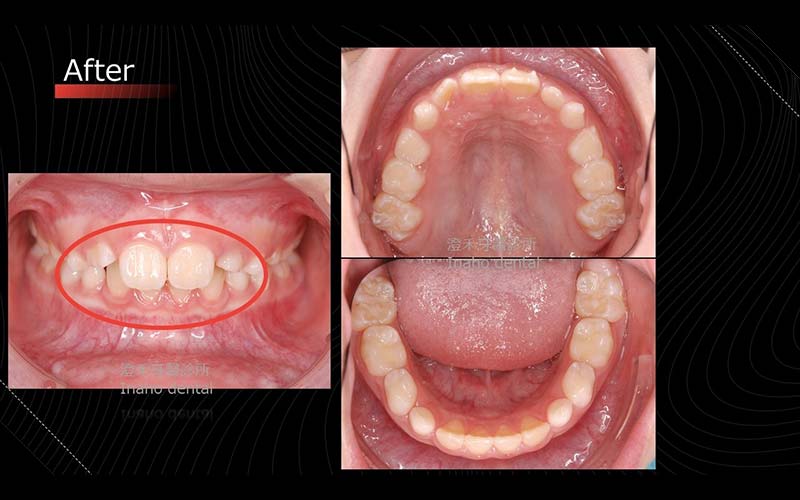

案例六

年齡:8歲

初期配戴MRC牙托,第二階段配戴隱適美矯正器,改善深咬、小下巴,以達到擴弓成果。

矯正療程:10M